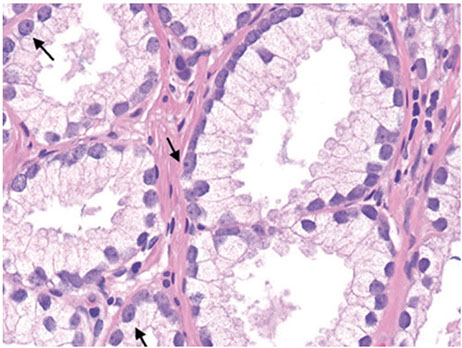

Central Zone Histology

Glands in the central zone at the base of the prostate are complex and alrge c lots of papillary infoldings and are often lined by tall pseudostratified epithelium c eosinophilic cytoplasm

- occasionally a prominent basal layer surrounds these glands, whereas in HG-PIN the basal layer is usually indistinct

- central zone glands are frequently dx'd as HG-PIN bc they have nuclei piled up and can be arranged in a Roman bridge and cribriform gland patterns

- of note, the central zone glands have nuclei that stream parallel to the glandular bridges, in contrast to the more rigid bridges seen in HG-PIN

- more importantly, central zone glands distinguished from HG-PIN by their lack of cytologic atypia

Central zone of prostate c Roman bridging